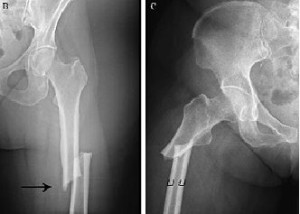

Los adultos mayores en el cuidado de ancianos contribuyen con el 30% de la carga social total de las fracturas de cadera. Las ingestas inadecuadas de proteínas y calcio son comunes en los adultos mayores que viven en hogares de ancianos. Mejorar la ingesta de proteínas y calcio a los niveles recomendados en adultos mayores en el cuidado de personas mayores redujo el riesgo de caídas y otras fracturas no vertebrales de cadera. Este enfoque nutricional para la prevención de fracturas resultó en un ahorro de costos. Age Ageing.. 1 de junio de 2023